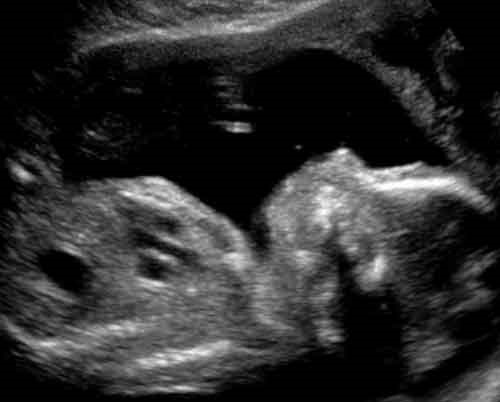

A magzat már a méhen belül gyakorolja a fájdalmas arckifejezést. A grimaszolással és sírással a kommunikációra készülnek - vélik a Durhami és a Lancasteri Egyetem kutatói.

Ultrahang-felvételek elemzése azt sugallja, hogy a várandósság során az egyszerű mosolytól az összetettebb szemöldök-ráncolásig és orrfelhúzásig fejlődnek a mozdulatok - mondták el tudósok a BBC hírszolgálatának. A kutatás vezetője, Nadja Reissland szerint a normális fejlődés megértése abban segíti az orvosokat, hogy a rendellenességeket kiszűrjék. "Nem világos egyelőre, hogy a magzat valóban tapasztal-e fájdalmat, és arckifejezései tükrözik-e, hogyan érzi magát" - magyarázta Reissland.

Az eredmények azt mutatják, hogy a grimaszok sokkal inkább az agy fejlettségétől, nem a tényleges testi érzetektől függnek. Nyolc lány- és hét fiúmagzat 4D-ultrahangképeinek videofelvételét vizsgálták meg a terhesség harmadik harmadában. A 24. hétben megfigyelt magzatok ritkán mutattak olyan mozdulategyüttest, amely fájdalmat fejezett volna ki. A 36. hétben viszont gyakori volt, hogy négy mozdulat kombinációjával fájdalmas arcot tudtak produkálni, ami arra enged következtetni, hogy minél érettebb a baba, annál inkább képes keserves arckifejezésre.